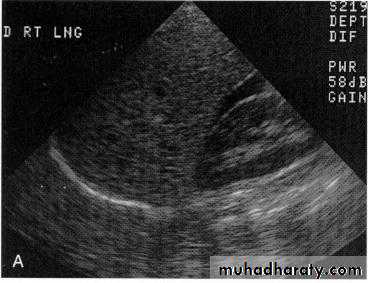

Spleen InjuriesInvestigation

FAST U\S abdomen .D.P.L.x-ray plain ,enlargement of splenic shadow

CT abdomen

Grading

Grade 1 – Minor subcapsular tear or haematoma

Grade 2 – Parenchymal injury not extending to the hilum

Grade 3 – Major parenchymal injury involving vessels and hilum

Grade 4 – Shattered spleen